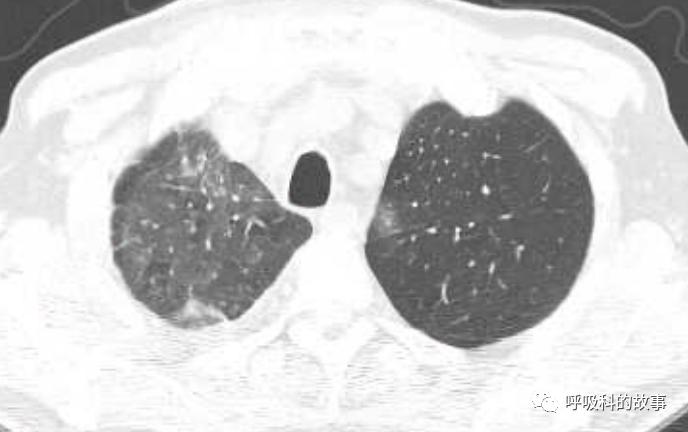

所以如果我们能对这些特征有所了解,那么其实诊断肺马尔尼菲蓝状菌感染并不是什么难事。后来我们又遇到一个肺部结节的患者(如下图):

大家可以发现这个小结节外周有晕征,内部有一小空洞,更重要的是纵隔淋巴结肿大,因此我们马上考虑到肺马尔尼菲蓝状菌感染,进行气管镜检查,做纵隔淋巴结穿刺培养出马尔尼菲蓝状菌。